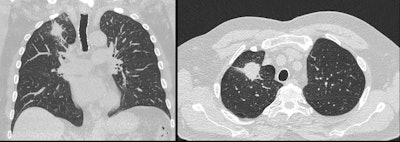

The Heart of Australia team diagnosed this former miner with lung cancer and emphysema using Philips’ Precise Image AI reconstruction app."Philips' software has significantly reduced the dose that was possible just with iterative reconstruction," Jones said. "Obviously we want to minimize the radiation dose given to our patients, but the underlying principle of diagnostic quality imaging is paramount; the worst case scenario is irradiating a patient only to find that the images are not of diagnostic quality."